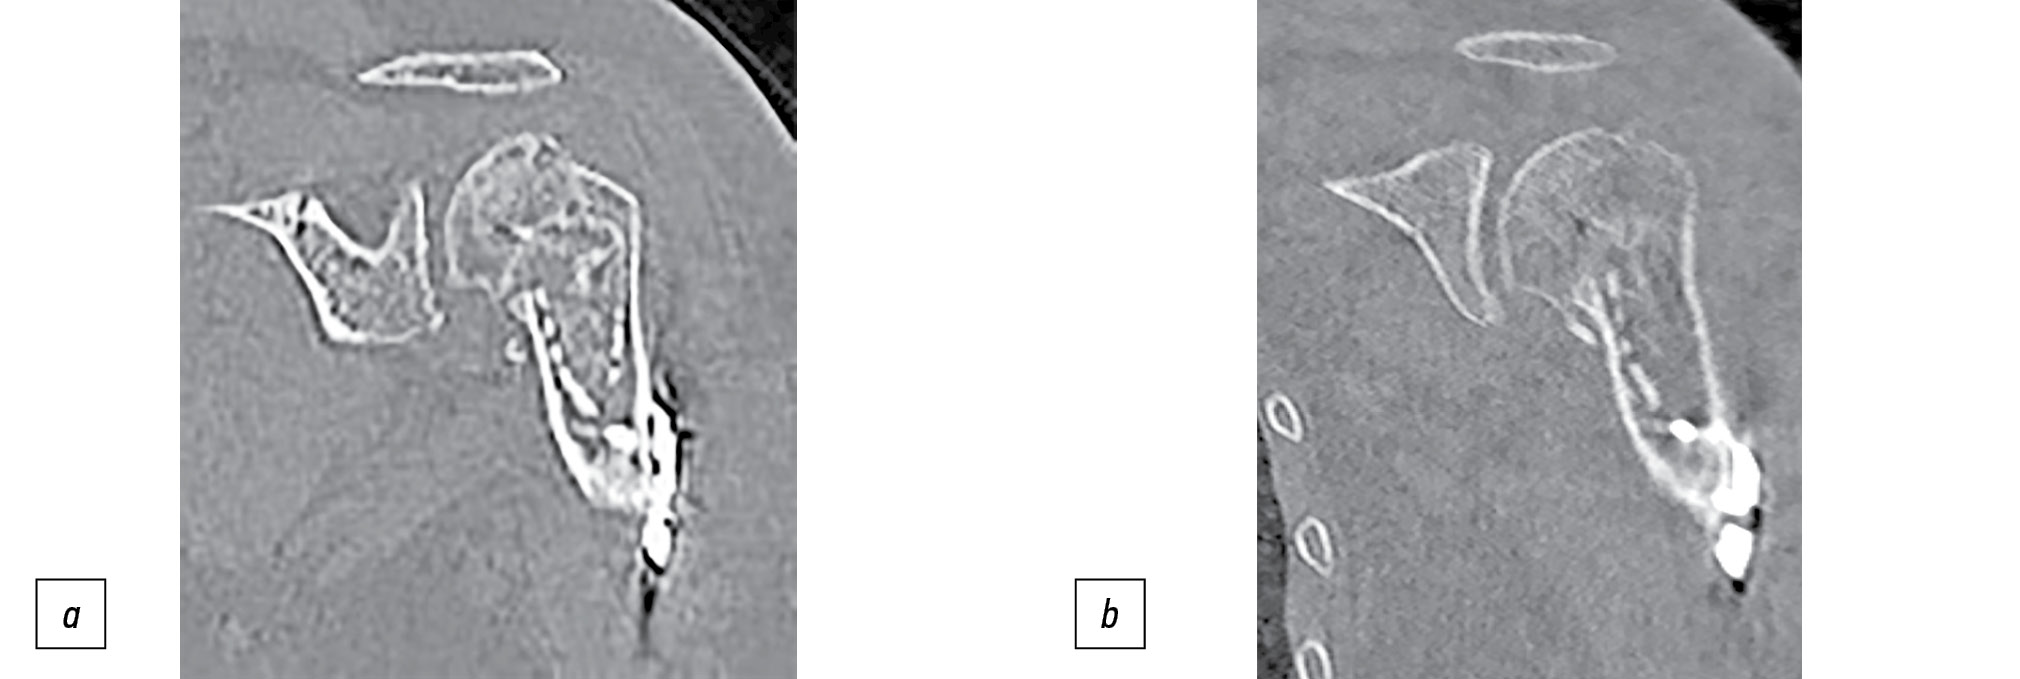

При МСКТ плечевого сустава в подгруппе О1 установлено, что у всех пациентов в течение года объём головки несколько уменьшился, но только у 2 (4%) человек это привело к прорезыванию винтов. В среднем объём головки плечевой кости после операции составил 50 (45,80) см3 (от, 43 до 88), через 1 год средний объём оказался равен 45 (35,80) см3 (от 40 до 76; р=0,133; W). Оценивали восстановление угла между головкой плечевой кости и диафизом (табл. 4). У всех пациентов при МСКТ с течением времени отмечали истончение кортикального слоя трансплантата и исчезновение границы между губчатой частью трансплантата и костной тканью головки плечевой кости, что считали признаками перестройки и лизиса трансплантата (рис. 6).

Рис. 6. Результаты компьютерной томографии сразу после операции (a) и через год после неё (b).

Fig. 6. CT immediately after surgery (a) and one year after surgery (b).